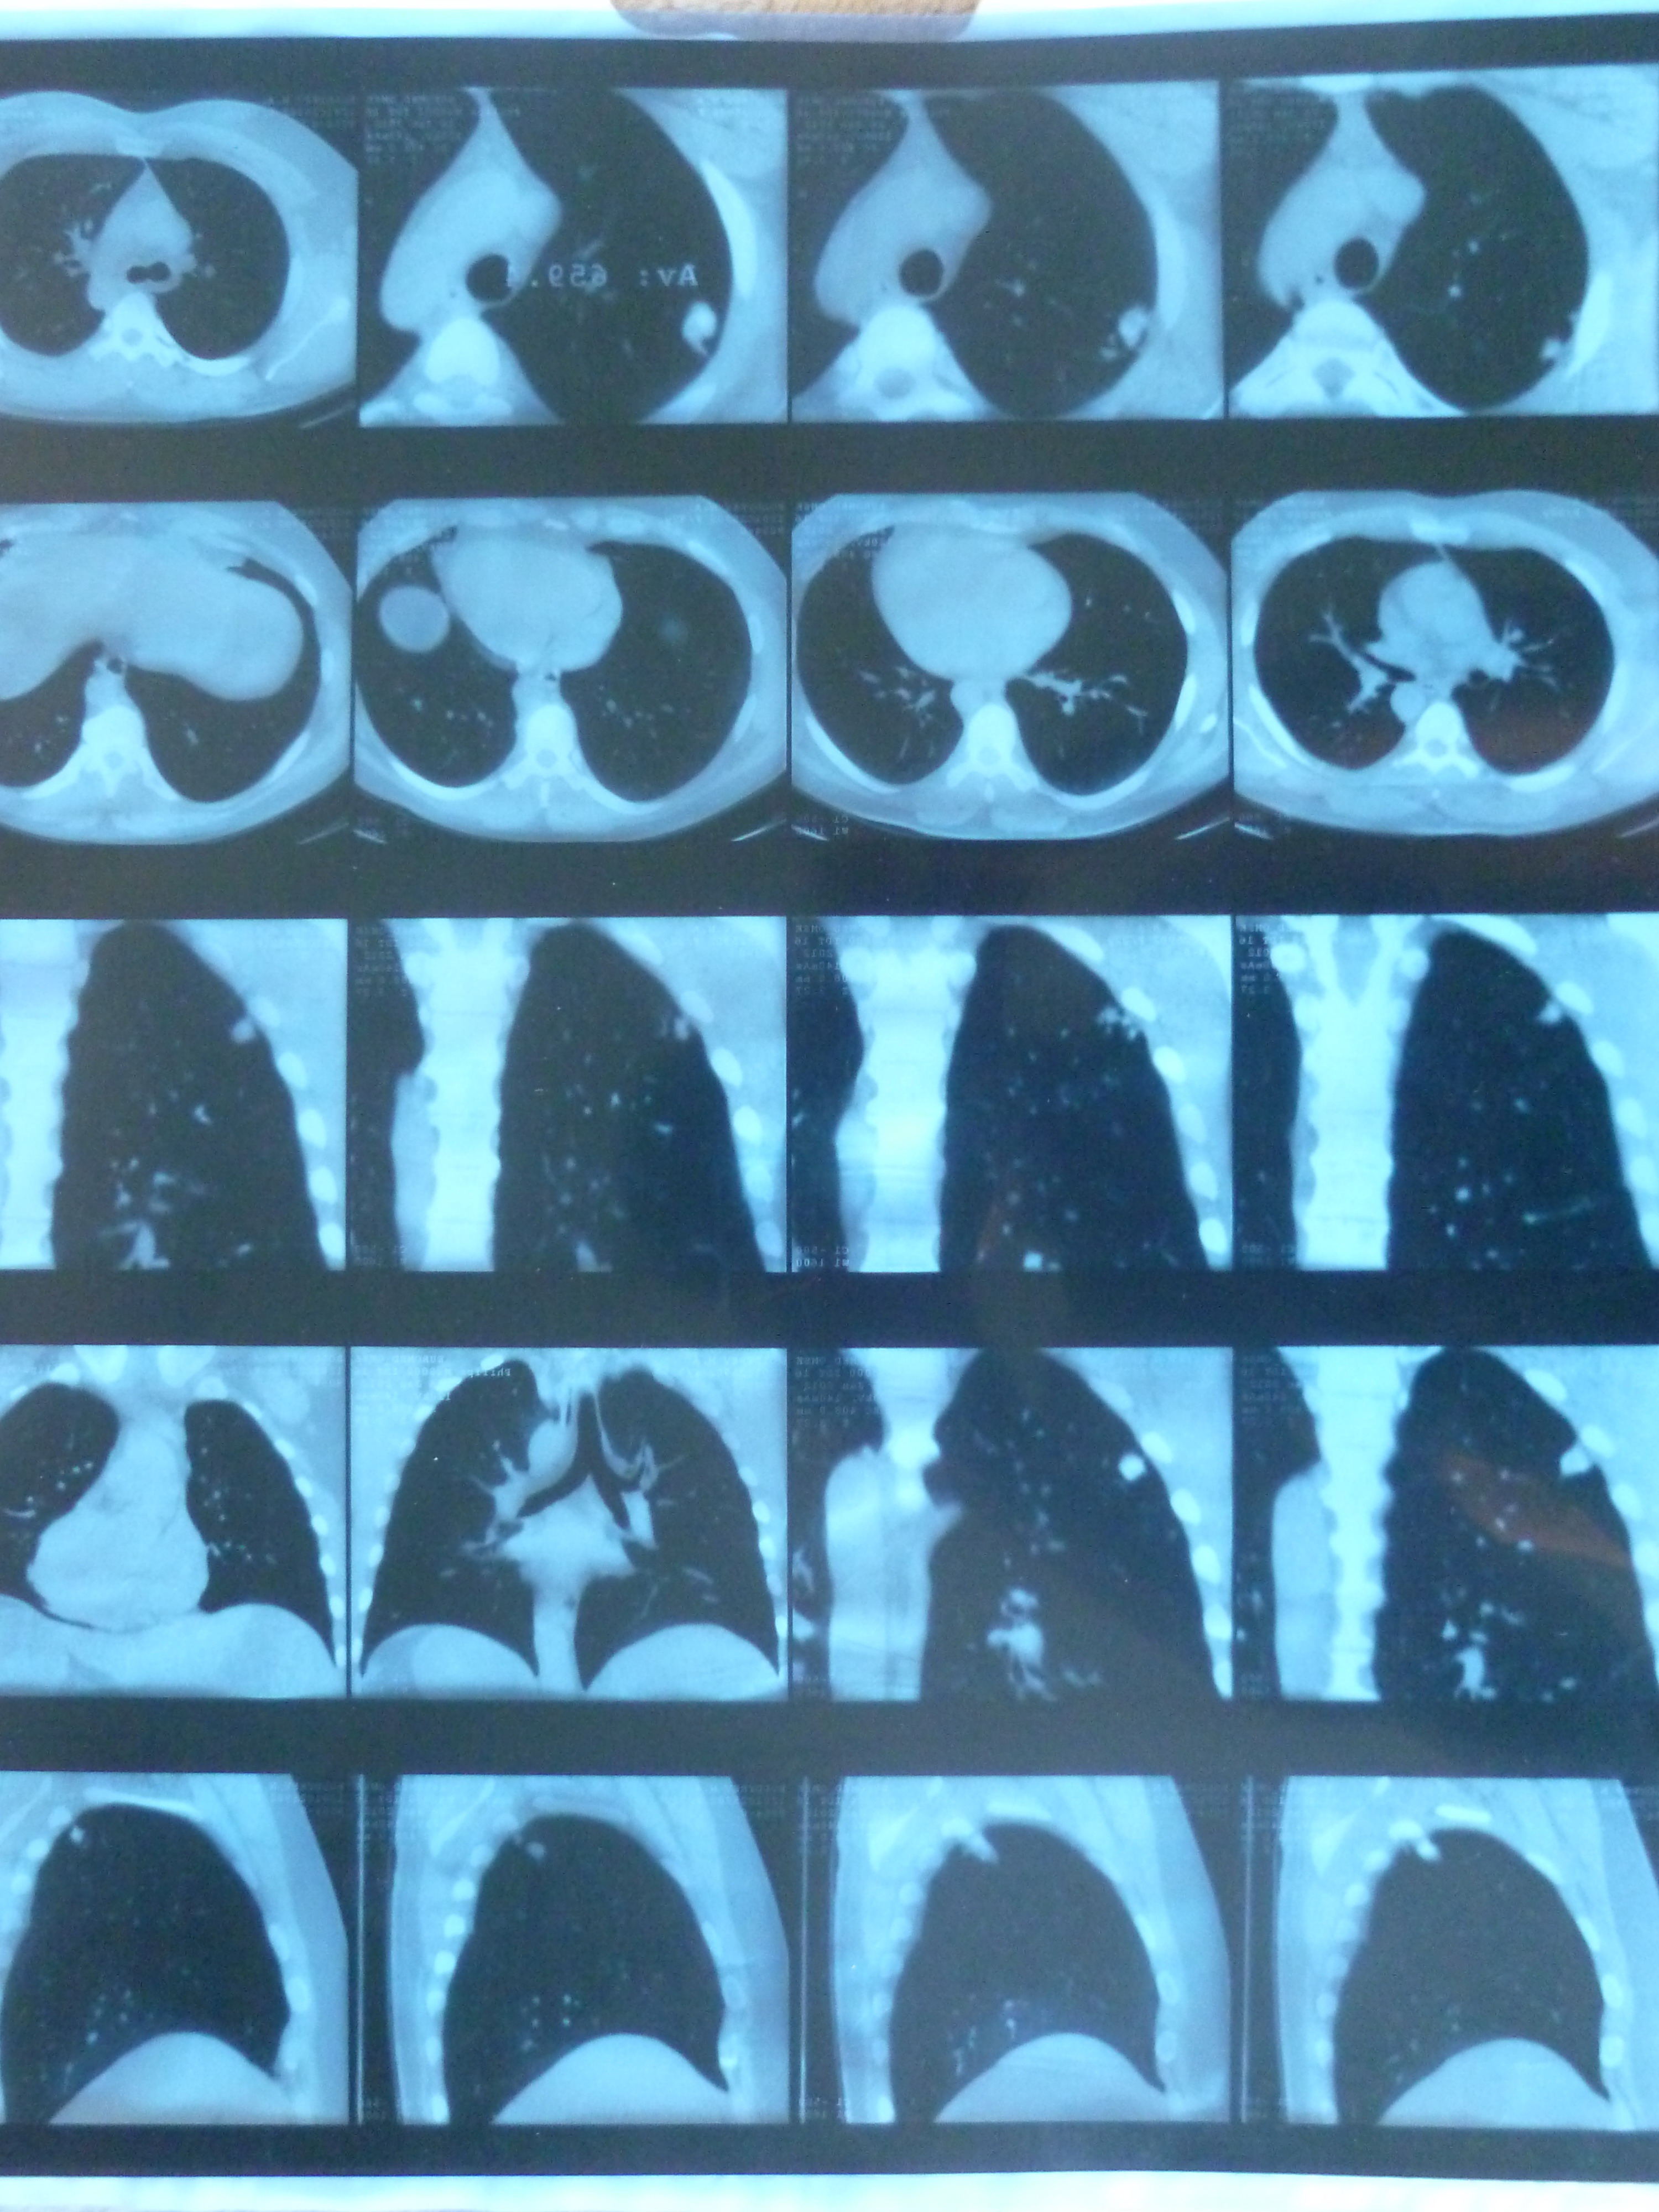

МСКТ: В латеральной кортикоплевральной зоне верхней доли правого легкого определяются 2 обызвествленных образования неправильной угольно-овальной формы, 24 мм и 13 мм в максимальном измерении, со спайками к паракостальной плевре. Очаговых и инфильтративных изменений в легких не определяется. Бронхопульмональные и паратрахеальные лимфоузлы не увеличены. Центральные бронхи без признаков патологических изменений. Средостение без особенностей. Плевральные синусы свободны. Косные структуры без деструкции. Заключение: кт-признаки 2 обызвествленных туберкулом верхней доли правого легкого.

Увы, выставленные Вами изображения весьма сомнительного качества.

Выставляйте на сайт изображения хорошего качества, тогда, возможно Вы получите адекватный ответ.